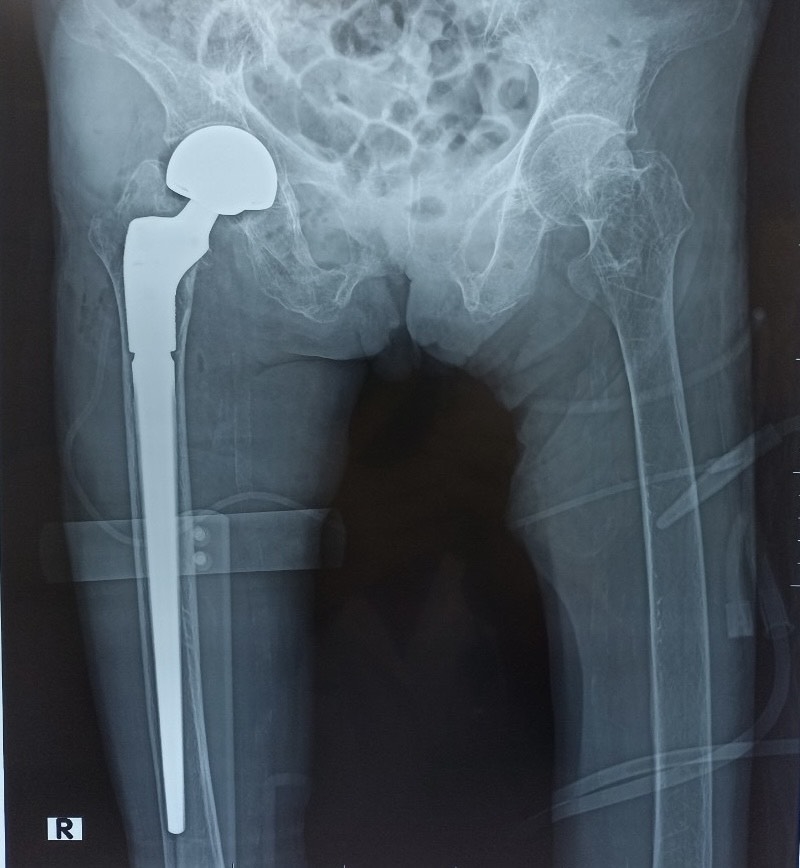

* Can Thiệp Ít Xâm Lấn và Ngoại Khoa: Đối với các trường hợp nặng như gãy xương phức tạp (ví dụ: gãy xương gót) hoặc thoát vị đĩa đệm nghiêm trọng, phẫu thuật có thể là cần thiết để cố định hoặc thay thế khớp bị hư hại. Các liệu pháp tiêm nội khớp (corticosteroid, huyết tương giàu tiểu cầu) cũng được áp dụng để giảm viêm và hỗ trợ tái tạo mô mềm. 4.2. Kết Hợp Với Y Học Cổ Truyền Trong Phục Hồi Chức Năng